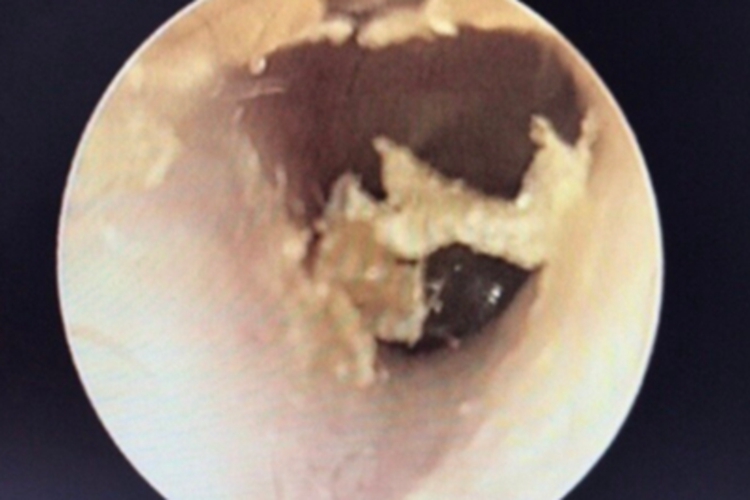

外耳道耵聍栓塞患者外耳道有白色分泌物,呈黏性,逐渐增大后形成黄白色鳞屑,并不断脱落,部分粘附在外耳道上,不断堆积后形成硬块。当出现完全堵塞时,可出现耳闷胀不适,伴听力下降、耳鸣,甚至眩晕等。

出现外耳道耵聍栓塞时,若出现明显不适症状,应及时就医,可在医生操作下,将耵聍取出,也可先用滴耳剂完全软化耵聍后用水将耵聍冲出。如遇不能用冲洗法取出耵聍的患者,可由专业医生用滴耳液软化耵聍后,再用吸引器慢慢将耵聍吸出。需注意,以上治疗均需遵医嘱进行。